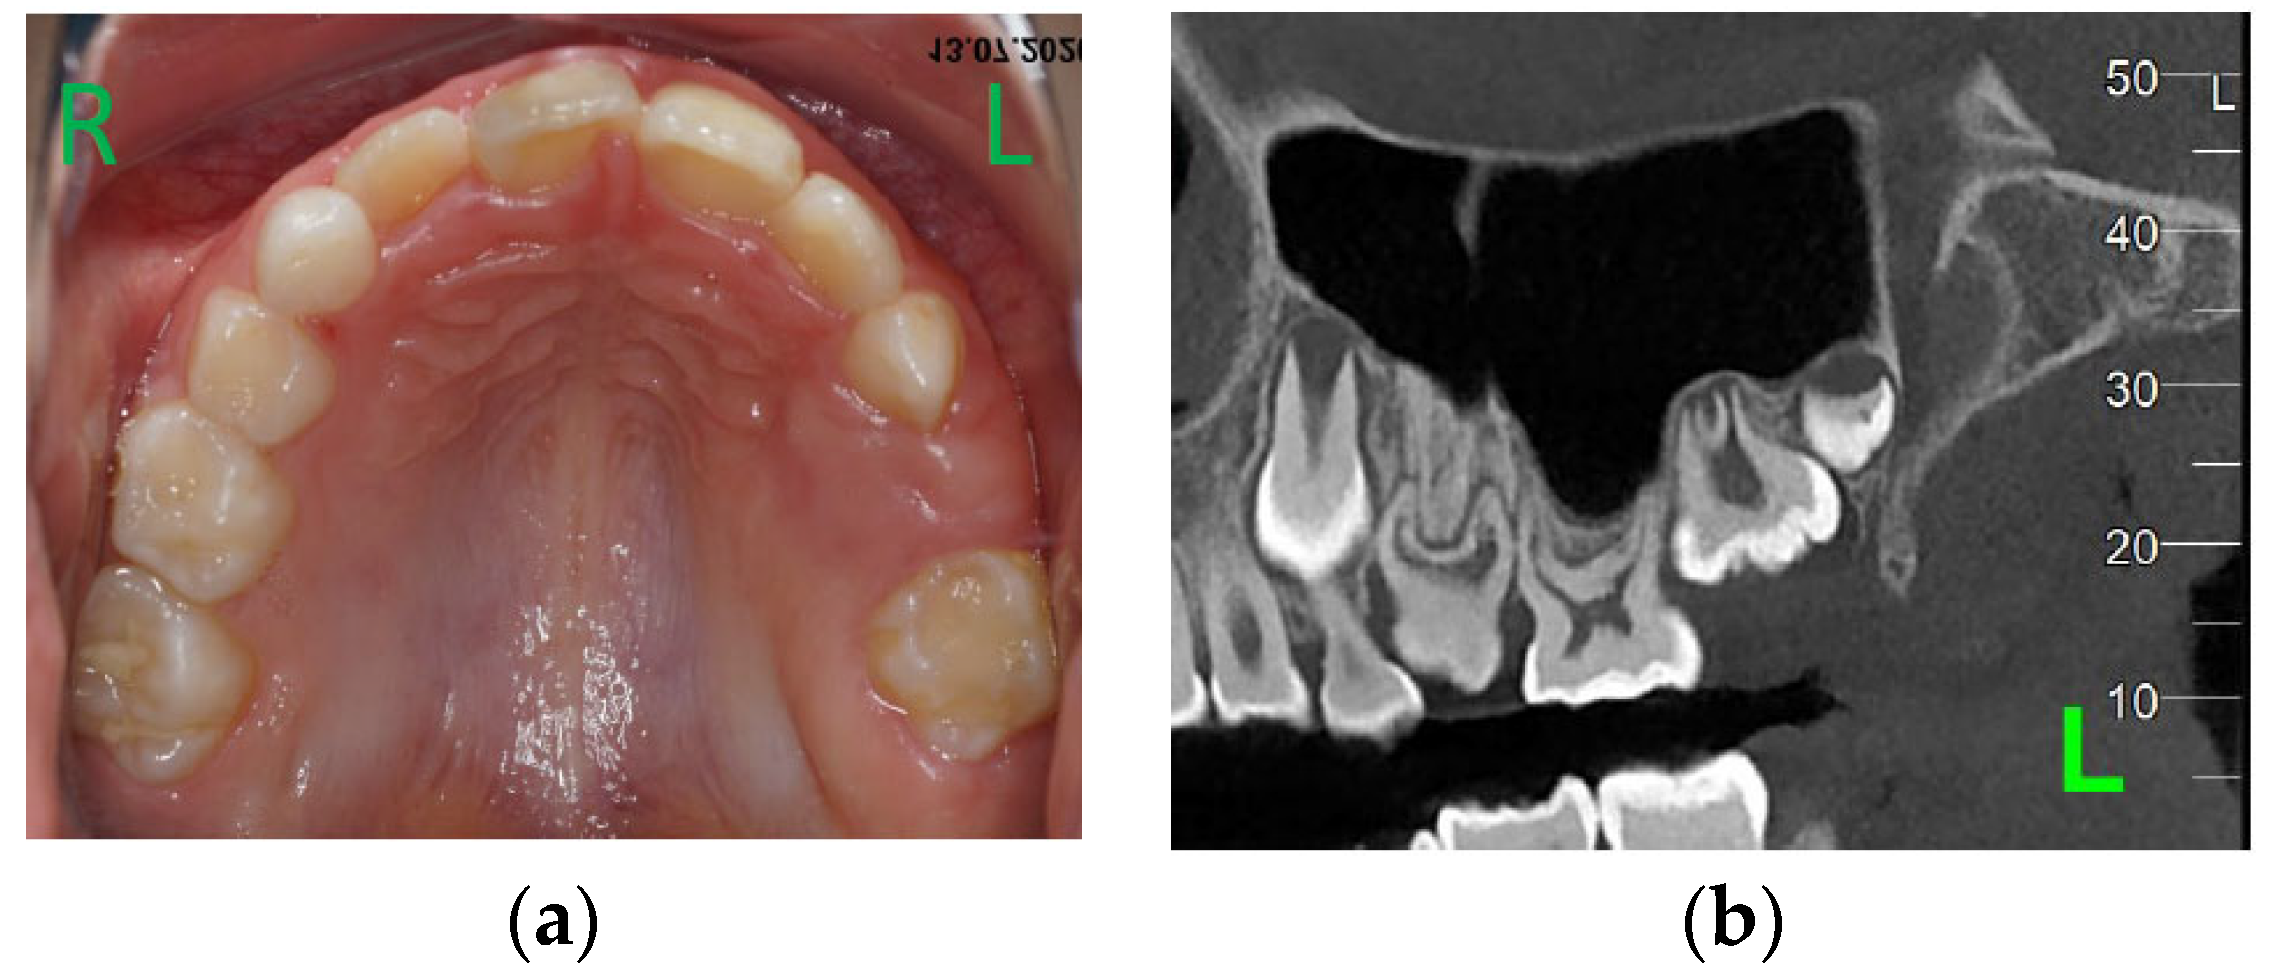

Clinical examination (Figure 1a) revealed no erupted teeth distal to the left upper canine, a left lateral open bite, and a slight shift of the upper midline to the left. Panoramic X-rays taken at this time showed delayed intraosseous development of the lateral left upper teeth as compared to the right side (Figure 1b) and no sign of mechanical obstruction. The agenesis of upper left premolars (24 and 25) was suspected but uncertain at the time.

Figure 1.

First visit; age of 4 y and 4 m. (a) Clinical aspect of the upper arch: no erupted teeth distal to the left upper primary canine; (b) panoramic X-ray.